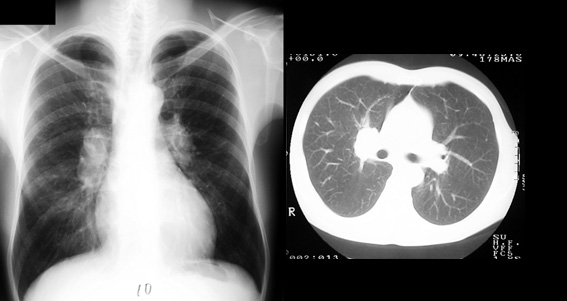

X線画像